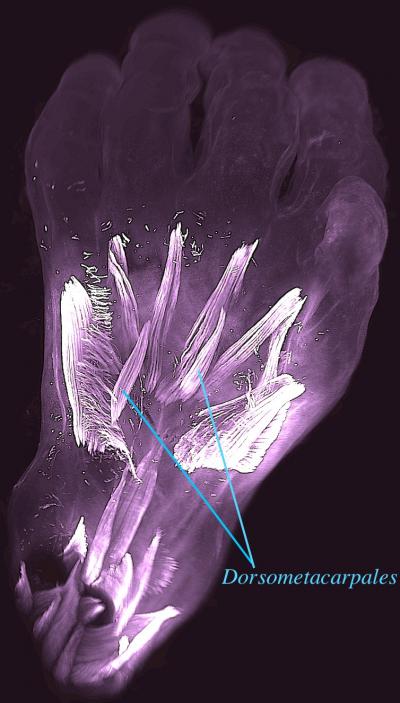

A team of evolutionary biologists, led by Dr. Rui Diogo at Howard University, USA, and writing in the journal Development , have demonstrated that numerous atavistic limb muscles - known to be present in many limbed animals but usually absent in adult humans - are actually formed during early human development and then lost prior to birth. Strikingly, some of these muscles, such as the dorsometacarpales shown in the picture, disappeared from our adult ancestors more than 250 million years ago, during the transition from synapsid reptiles to mammals.

Also remarkably, in both the hand and the foot, of the 30 muscles formed at about 7 weeks of gestation one third will become fused or completely absent by about 13 weeks of gestation. This dramatic decrease parallels what happened in evolution and deconstructs the myth that in both our evolution and prenatal development we tend to become more complex, with more anatomical structures such as muscles being continuously formed by the splitting of earlier muscles. These findings offer new insights into how our arms and legs evolved from our ancestors’, and also about human variations and pathologies, as atavistic muscles are often found either as rare variations in the common human population or as anomalies found in humans born with congenital malformations.